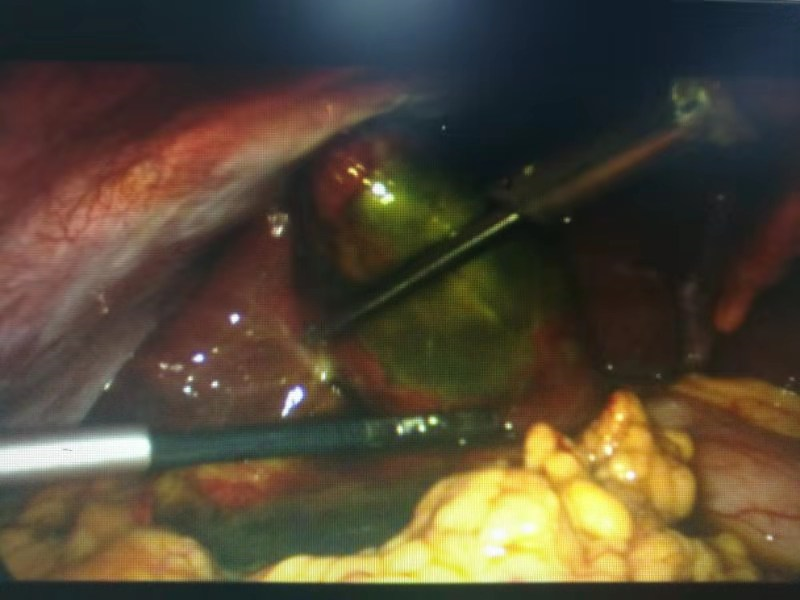

有了周詳?shù)挠媱?,?jīng)過充分的術(shù)前準備,手術(shù)開始了。從腹腔鏡下發(fā)現(xiàn),患者膽囊底部壞疽穿孔,膽囊周邊有膽汁滲出。一個小時左右,壞疽膽囊和膽結(jié)石被成功取出。

患者術(shù)中照片